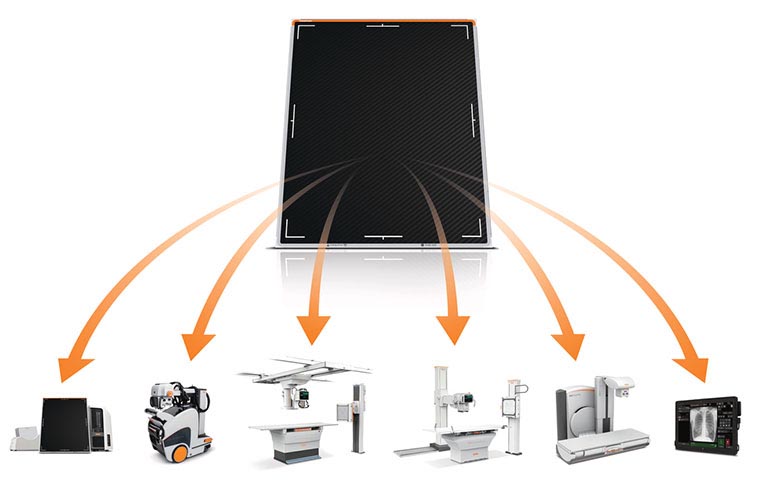

Carestream Focus HD 35/43 Retrofit Detectors Powered by Image Suite Software

High-Definition Detectors for Ultra-Detailed Imaging

By Praveen Rajgopal, Global Product Marketing Manager

Upgrading your imaging system to a solution designed for outstanding image quality is no longer out of reach — it's now easier, more affordable, and more effective than ever before.

Our Carestream Focus HD 35/43 Retrofit Detectors, powered by Image Suite Software, are an ideal solution to step up to full digital X-ray for customers who simply cannot compromise on image quality. It seamlessly integrates into existing setups, bringing the power of full digital X-ray with minimal disruption and maximum clarity, along with the following benefits: